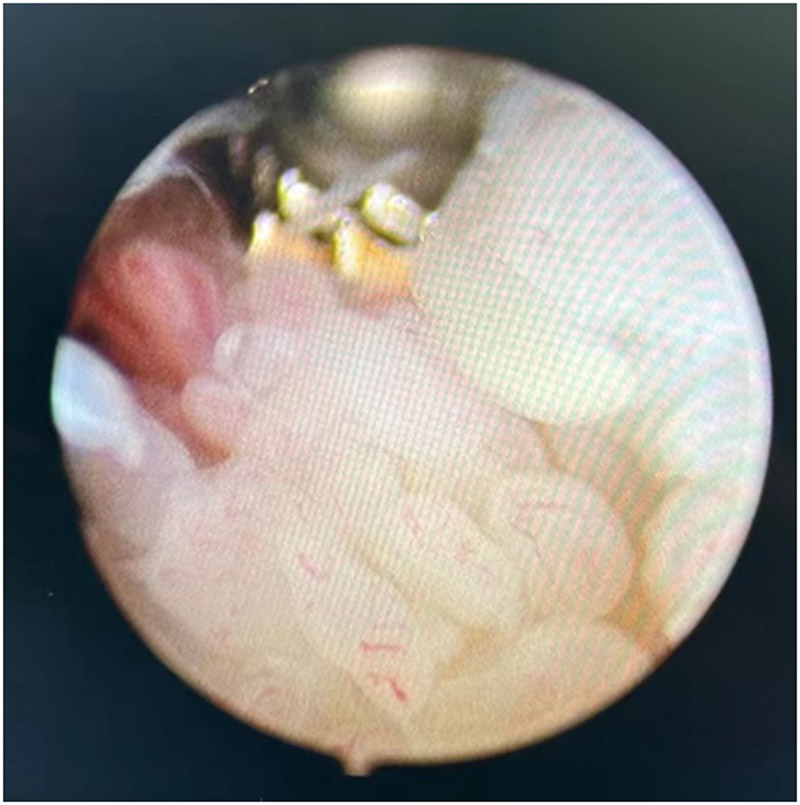

做好充分的術(shù)前準(zhǔn)備后,醫(yī)生使用關(guān)節(jié)鏡微創(chuàng)技術(shù),通過2個(gè)0.5厘米大小的切口為丁伯進(jìn)行了關(guān)節(jié)鏡下的滑膜清理手術(shù)治療。術(shù)中發(fā)現(xiàn)腕關(guān)節(jié)內(nèi)大量的炎性增生滑膜,部分滑膜已經(jīng)開始侵蝕關(guān)節(jié)軟骨。這些像水草一樣的增生滑膜正是丁伯腕關(guān)節(jié)反復(fù)腫脹疼痛的罪魁禍?zhǔn)住?/span>